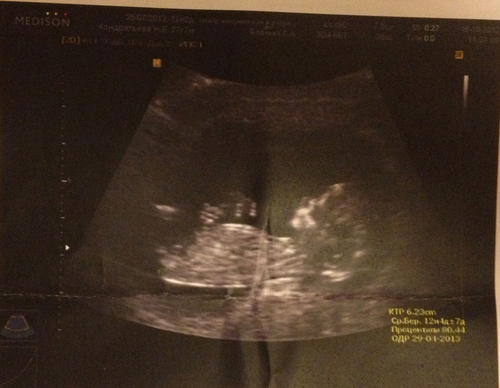

УЗИ на 21 неделе беременности

Развитие малыша происходит на каждой неделе «интересного положения». И если у вас все идет в положительно динамике, то доктор на 21 неделе обычно назначает второе плановое УЗИ всех триместров. В ходе ультразвукового обследования врач расскажет о таких моментах:

- нормально ли развивается плод;

- есть ли какие-то угрозы;

- подтвердить или в первый раз сообщить пол малыша;

- насколько малыш активен и крепок.

УЗИ на 21 неделе – необходимая процедура, которая поможет оценить состояние ребеночка и уровень его развития. Кроме того это хорошая возможность исключить наличие патологий. В ходе обследования доктор внимательно осмотрит органы малыша и сопоставит их размеры, габаритам плода. На основании этих данных составляются выводы о характере течения беременности.